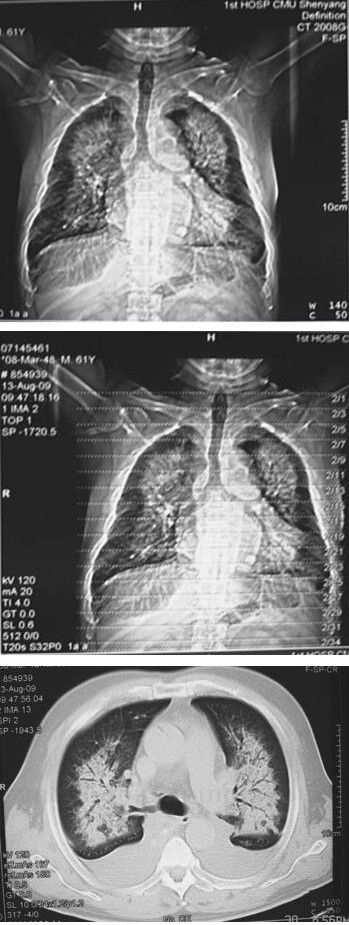

8. 胸部CT

提示急性肺水肿。入院当天胸部CT见图2-2,入院第3天胸部CT见图2-3。

图2-2 胸部CT检查(入院当天)